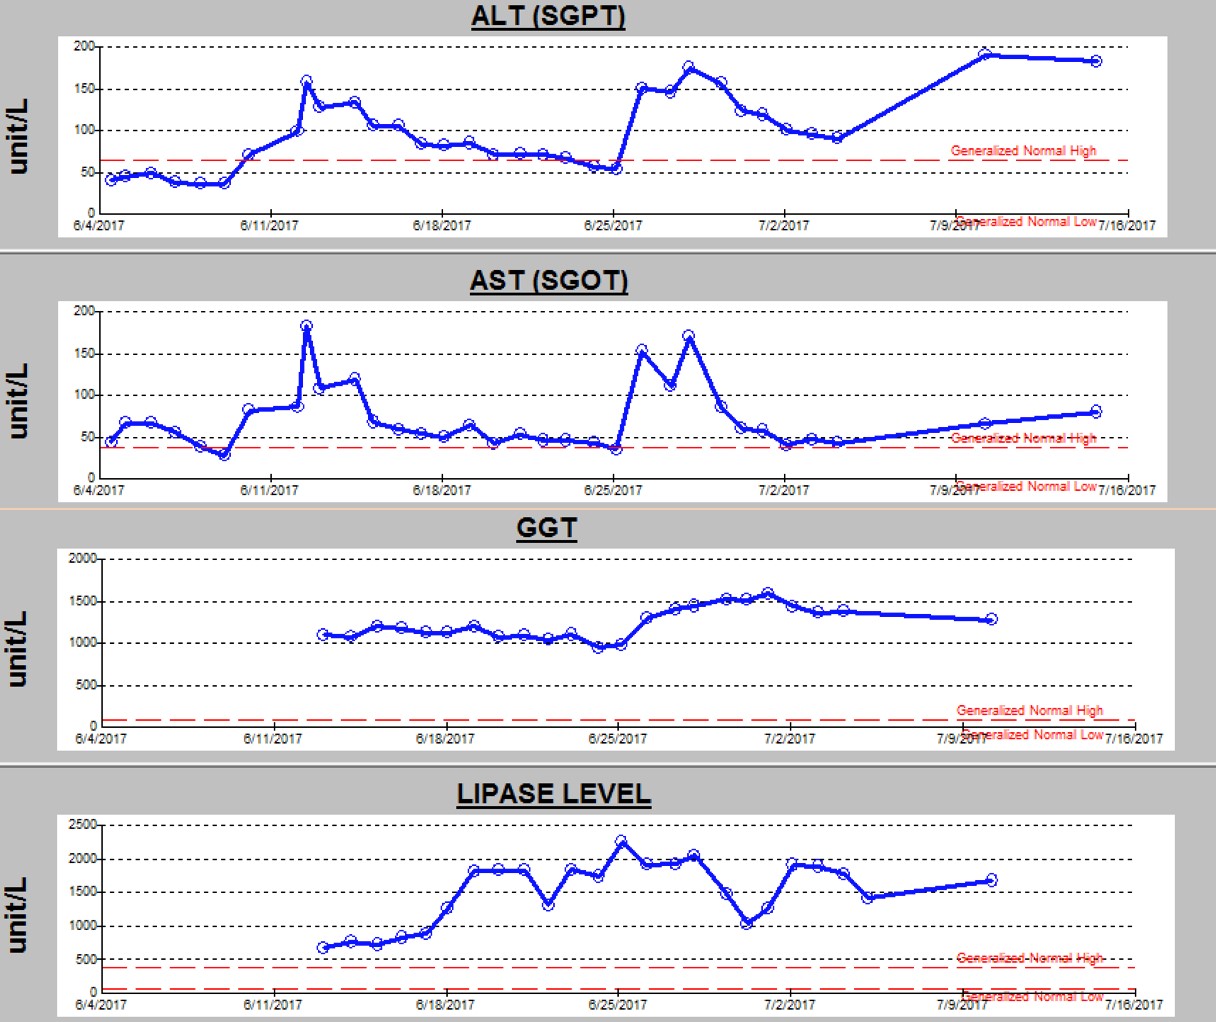

An electroencephalogram (EEG) during the current admission showed frequent multifocal epileptiform discharges, which was a finding similar to that of his prior EEGs. Since he had continued to have breakthrough seizures despite 3 antiepileptic drugs (phenobarbital, levetiracetam, and lacosamide), a fourth antiepileptic drug (clobazam) was added. The seizures improved, but his liver function test (LFT) results, which included alanine aminotransferase (ALT), aspartate aminotransferase (AST), and γ-glutamyltransferase (GGT), and his lipase level, showed abnormal elevations for 3 days after addition of clobazam (Figure 2).

Figure 2. Trend of ALT, AST, GGT, and lipase levels during the current hospital stay.

Clobazam was discontinued out of concern for possible drug-related adverse effects, but LFT results continued to remain elevated. The serum amylase level and abdominal ultrasonography findings were normal, which ruled out pancreatitis and other abnormalities of the hepatobiliary system. MRI with magnetic resonance spectroscopy of the brain (Figure 3) demonstrated a new area of involvement in the left occipital lobe.